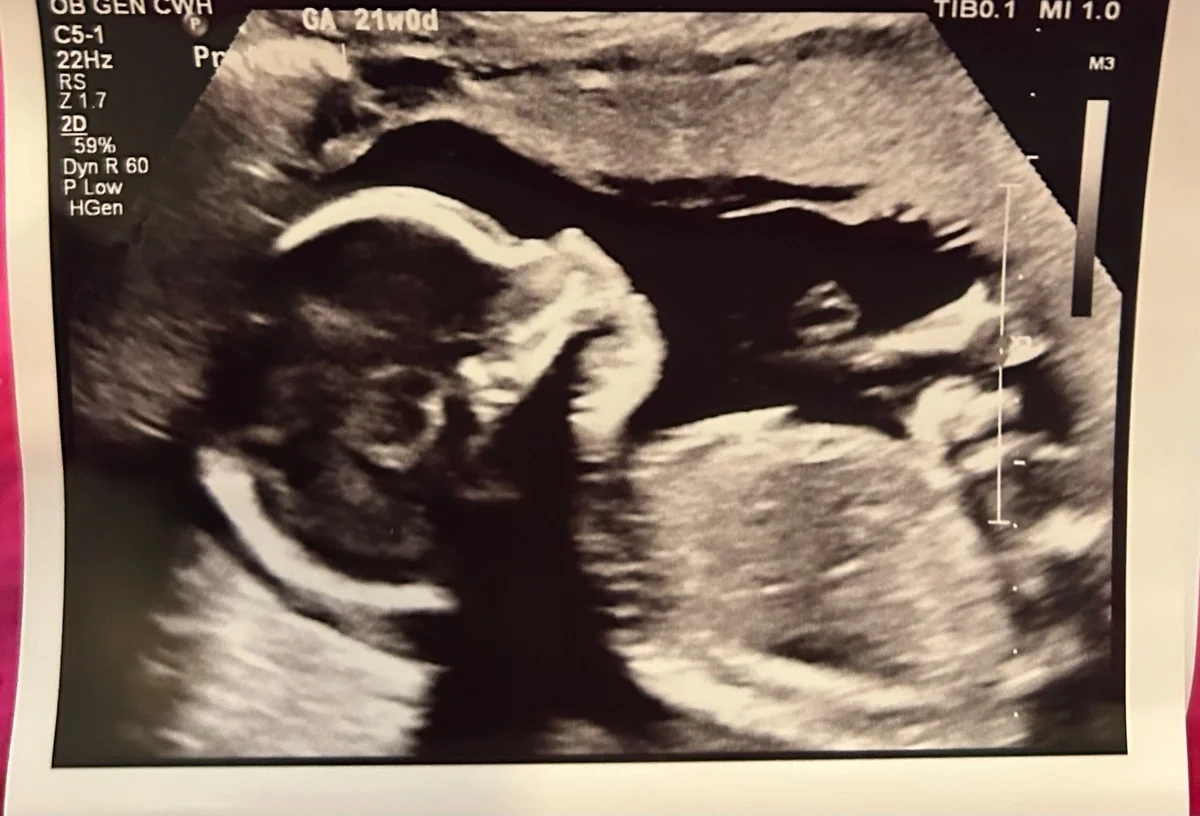

Melissa underwent two egg retrieval cycles and six of her embryos were genetically tested. Two turned out to be euploid embryos, and her embryo transfer took place a few days before Christmas 2024.

The two week wait was one of the hardest periods for Melissa emotionally. “I Googled every symptom and tried not to get my hopes up, but the anticipation was killing me. When the nurse finally called to confirm we were pregnant, I had never felt so relieved, excited and scared all at once. It was like I was dreaming.” Melissa and Steven’s daughter, Ruby Grace Cooper, was born on September 5, 2025!

One of the most empowering moments came during her first ultrasound after the positive pregnancy test. “Our doctor said everything looked ‘textbook perfect,’” Melissa recalls. “Realizing that my body had responded to treatment was incredibly rewarding. Of course, delivering our sweet girl and now having her home with us is the cherry on top!”